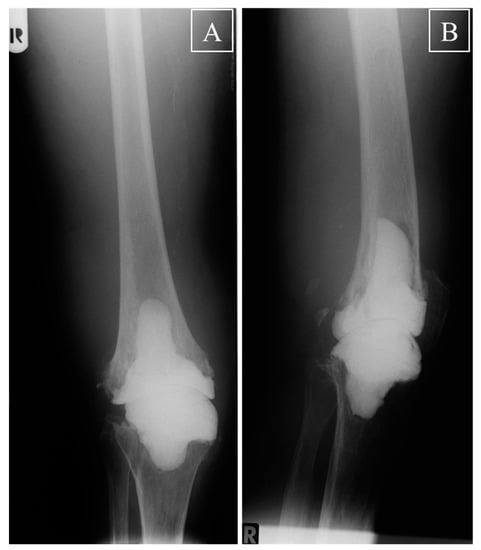

For the first time, the present spacer was designed as a stem-reinforced, inverse spacer with a convex tibial and a concave femoral component (Figure 1A,B).

The advantages of this design are the following: (i) tight embracing of the convex tibial part by the concave femoral part recalls pure hinge joints such as the elbow joint, in which approximately 50% of the convex trochlea is covered by the concave ulna. This shape sufficiently prevents anterior to posterior (ap) translation of the spacer; (ii) the usually smaller bone defect on the tibia, in conjunction with its anatomic shape and its levelled, broad weight-bearing surface, suggested a convex shape on the tibia. In contrast, the larger, anatomically concave femur defect with the central notch rather suggested a concave shape of the femoral component; (iii) after initial molding and polymerization of the tibial component, molding of the concave femoral component under maximal tension turned out straightforward and efficient, allowing to adapt the two spacer components with minimized play until the last minute of the polymerization. In addition, both parts of the spacer were designed with a stem component to ensure optimal anchoring in the medullary canal for rotational stability [11,14].

Early mobilization under sole contact with crutches or other devices was excellently tolerated by all patients without clinical signs of dislocations, subluxations, fractures of spacer or bone, or soft tissue compromise requiring reoperation. X-rays taken before re-implantation also did not show any indications for dislocation, subluxation, fractures of spacer or bone, or increased gross abrasion of bone in the joint area in any patient (Figure 2A,B), resulting in a calculated Kaplan–Maier failure rate of zero for the spacers.

The advantages of the current two-component spacer with restricted post-operative ROM in comparison with a conventional static spacer can thus be summarized as follows: (i) by reducing the post-operative forces/friction occurring at the cement-spacer interface, the current spacer design may help to avoid gross bone loss and bone fractures, as exemplified in representative Figure 2; (ii) in comparison to a large, more bulky one-component static spacer, the two segments of the current spacer appear to simplify and optimize the preparation and implantation of the spacer, including a more convenient sequential pre-forming, insertion, molding, and hardening of the separate components under conservation of the appropriate joint length and tension; (iii) the current spacer may allow an easier and less time-consuming removal of the spacer during re-implantation TKA. A spacer design with a convex femoral component and a concave tibial component with a higher anterior and posterior lip may also be suitable to avoid anterior or posterior luxation, but may be more susceptible to damage by high axial forces acting on the spacer.

Figure 2. Knee X-ray before re-implantation. (A) Anterior to posterior and (B) lateral X-ray of a right knee with the inverse spacer of one representative patient before re-implantation TKA. A perfect fit of the two different spacer components into the tibial and femoral medulla was observed, without any signs of dislocation, subluxation, fractures of spacer or bone, or increased gross abrasion of bone in the joint area; R = right.